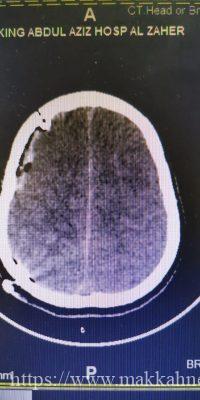

نجح فريق جراحة المخ والأعصاب بمستشفى الملك عبدالعزيز بمكة، عضو التجمع الصحي بمكة المكرمة – بفضل من الله – والامكانيات المتوفرة من انقاذ حياة مصاب يبلغ من العمر ١٤ عاماً من الوفاة الدماغية .

أوضح استشاري ورئيس قسم جراحة المخ والأعصاب، قائد الفريق الطبي الدكتور زهير هوساوي، أن المريض حضر لقسم الطواري والحوادث وهو يعاني من اصابة مباشرة في الدماغ وفقدان الوعي كاملاً اثر حادث مروري وبعد اجراء الفحوصات والاشعه اللازمة تبين وجود نزيف سطحي مع ضغط على جذع الدماغ مع بوادر الوفاة الدماغية وعلى إثر ذلك تم تجهيز المريض في قسم الطوارى الى غرفة العمليات خلال ١٥ دقيقة واجريت العمليه للمريض بمشاركة الفريق الطبي المكون من د. محمد المشد جراح مخ واعصاب ود. هاني محبوب اخصائي جراحة مخ واعصاب ود. عبدالرحمن الصائغ طبيب جراحة المخ والاعصاب ود. علي الغامدي استشاري تخدير حيث تمت إزالة النزيف عن طريق المايكرسكوب الجراحي والمحافظه على انسجة الدماغ بتقنية التبريد الدماغي خلال العملية التي استغرقت ساعتين وتمت مرافقة المريض في العناية المركزه لمدة ٢٤ ساعه وبعد اجراء العملية بثلاثه ايام خرج المريض من المستشفى وهو بصحه جيده ولله الحمد